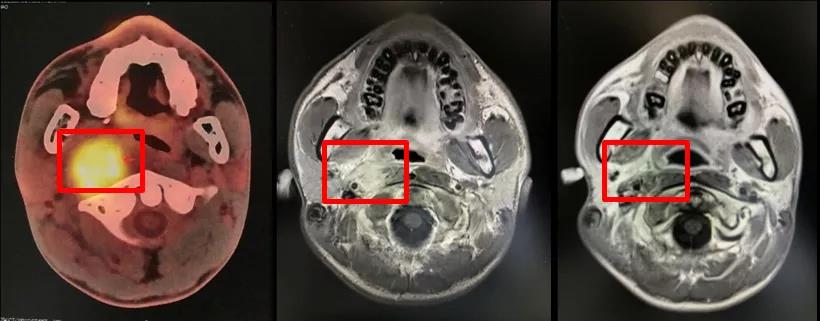

影像学评价:鼻咽MR(2020年3月24日),治疗前后MR变化见图2,可见鼻咽顶后壁黏膜增厚,范围约10mm*10mm;右侧颈部II-V区多发转移淋巴结,大者直径约10mm,病灶较前缩小。右髂骨转移瘤,直径约20mm,强化明显。

影像学评价:鼻咽MR(2020年7月7日),治疗前后MR变化见图2,可见鼻咽顶后壁黏膜增厚,范围约5mm×5mm;右侧颈部II-V区多发转移淋巴结,大者直径约5mm,病灶较前进一步缩小。右髂骨转移瘤,直径约20mm,范围较前变化不大,强化较前减低。如图2-1(鼻咽部病灶)、2-2(右侧颈部淋巴结病灶)、2-3(右侧髂骨病灶)从左至右分别为治疗前(2020年2月17日)、4程治疗后(2020年3月24日)、放疗后1个月(2020年7月7日)。